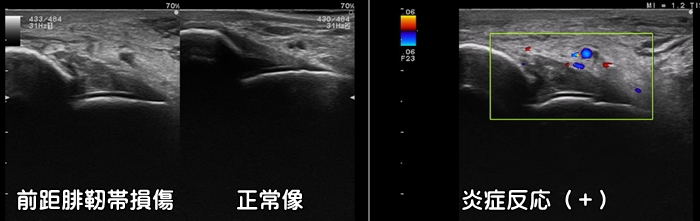

足首の捻挫・前距腓靭帯損傷

足首の捻挫で最も損傷を受ける靭帯が前距腓靭帯です。エコー検査では靭帯の断裂の有無を確認できます。特に子供では剥離骨折を合併するリスクが高い為に要注意です。初期の適切な治療が重要です。炎症反応の動画はこちらで確認できます。